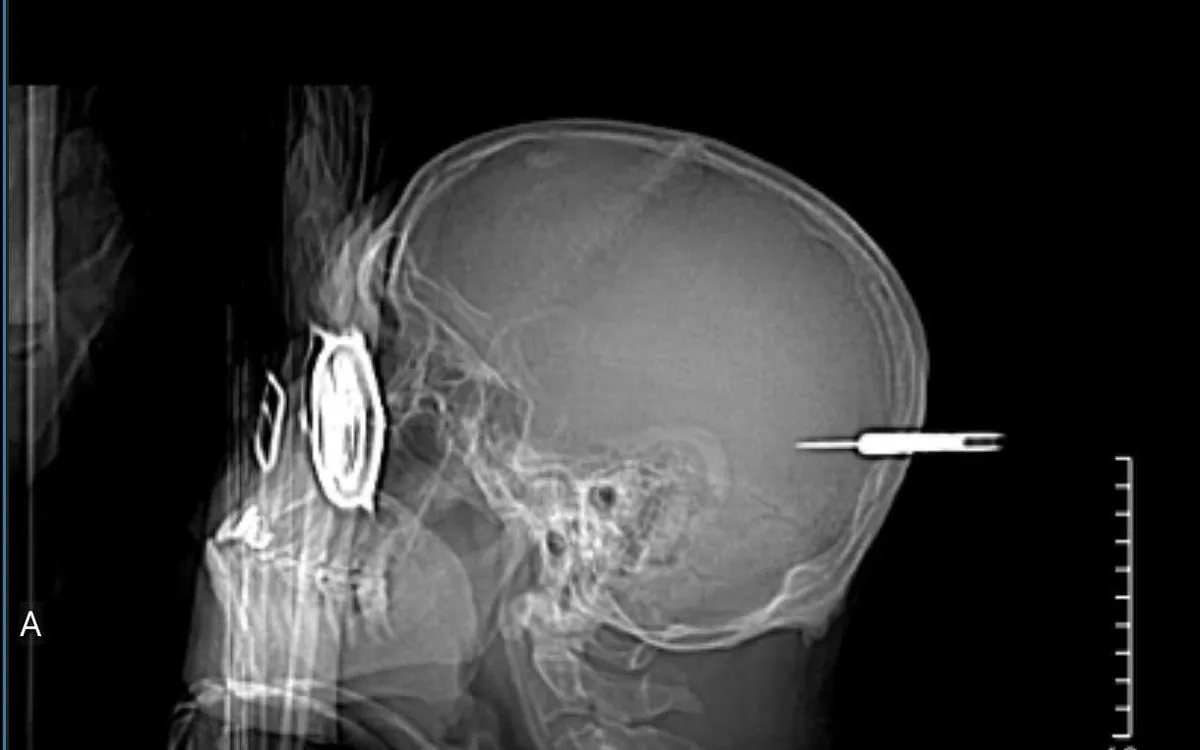

Bệnh nhân nam, 66 tuổi, bị một mũi phi tiêu ném trúng vùng đầu khi đang tham gia hoạt động vui chơi. Người bệnh nhập viện trong tình trạng chấn thương sọ não và đã được cấp cứu khẩn cấp để lấy dị vật.